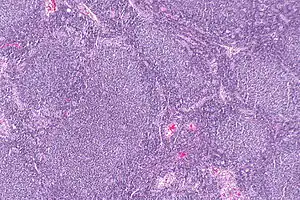

Follicular lymphoma (FL) is a cancer that involves certain types of white blood cells known as lymphocytes. The cancer originates from the uncontrolled division of specific types of B-cells known as centrocytes and centroblasts. These cells normally occupy the follicles (nodular swirls of various types of lymphocytes) in the germinal centers of lymphoid tissues such as lymph nodes. The cancerous cells in FL typically form follicular or follicle-like structures (see adjacent Figure) in the tissues they invade. These structures are usually the dominant histological feature of this cancer.[1]

| Micrograph of a follicular lymphoma, showing the characteristically abnormal lymphoid follicles that gave the condition its name. H&E stain. | |

The diagnosis of FL depends on examining involved tissues for histological, immunological, and chromosomal abnormalities that are indicative of the disease. FL usually involves enlarged lymph nodes populated by abnormal follicles (see adjacent picture) that when examined histologically contain a mixture of centrocytes or centroblast surrounded by non-malignant cells, mostly T-cells. The centrocytes, which typically outnumber centroblasts, are small to medium-sized B-cell lymphocytes that characteristically exhibit cleaved nuclei; the centropblasts are larger B-cell lymphocytes without cleaved nuclei.[11] Rare cases of FL may show lesions that contain tissue infiltrations dominated by B-cells with features of precursor (i.e. "blast") cells, monocytes, or malignant mantle cells such as those found in mantle cell lymphoma.[1] Immunochemical analyses reveal that these cells generally express B-cell surface markers including the CD10 (60% of cases), CD20, CD19, CD22, and CD79 but not CD5, CD11c, or CD23 cell surface proteins;[4] genomic analyses reveal that these cells contain t(14:18)(q32:q21.3) translocation (85-90% of cases), 1p36 deletions (60-70% of cases), and with far less frequency the other genomic abnormalities listed in the above sections on Pathophysiology and Presentation and course. None of these protein markers or genomic abnormalities are diagnostic for FL, e.g. the t(14:18)(q32:q21.3) translocation is found in 30% of diffuse large B-cell lymphoma and in a small number of reactive benign lymph nodes. Rather, the diagnosis is made by a combination of histological, immunological, and genomic abnormalities.[4] According to World Health Organization (WHO) criteria, differences in the microscopically-determined morphology of these tissues can be used to diagnose and categorized FL into the following 3 Grades with grade 3 having A and B subtypes:[51]